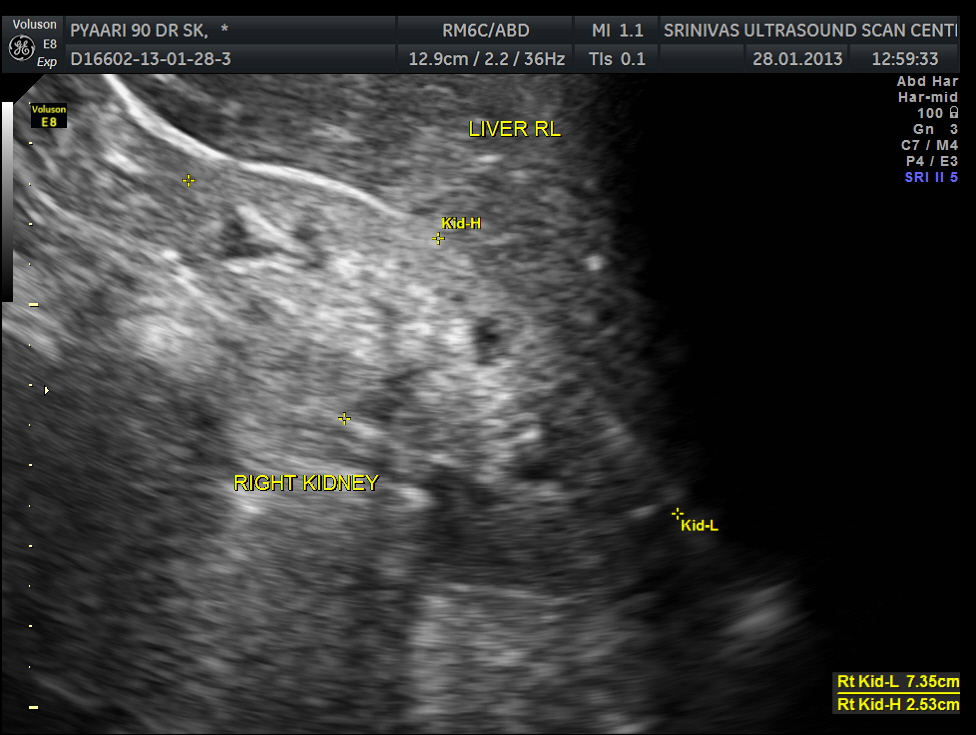

Both kidneys show features of medical renal disease.